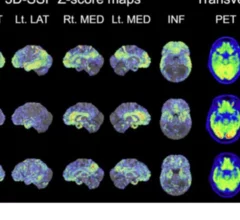

Physicians utilize medical imaging to see inside the body to diagnose and treat patients. This includes computed tomography (CT), magnetic resonance imaging (MRI), X-ray, ultrasound, fluoroscopy, angiography, and the nuclear imaging modalities of PET and SPECT.